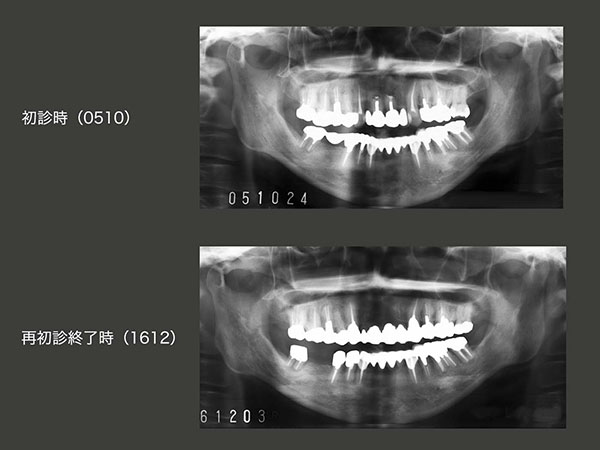

1994年初診,59歳の女性.主訴は下顎の義歯が合わないで,同年新規に製作した.また,95年7月から右上5から左上5のブリッジの新規製作に取りかかり,12月に完成した.スライド下のパノラマX線写真は,94年初診時および98年時の状態.

2014年1月,上顎ブリッジ製作後18年2ヵ月の状態.上顎は,一見問題なさそうであるが,パノラマX線写真から右上4,左上5に明らかなう蝕が認められた.また,右上3,4は,98年にコンポジットレジン修復を行ったが,完全にう蝕を取り除けたかどうか不安であった.このまま放置し,う蝕がさらに進行してしまうと,これらの歯を失う危険があることから,ブリッジの再治療を提案させて頂き,患者さんの承諾を得た.なお,下顎のインプラントは09年に施術した.この頃が私のインプラントの全盛時代であった.